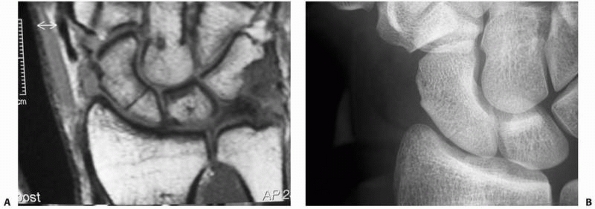

![]() |

|

FIGURE 29-16 A. The MRI scan demonstrates a clear fracture line of the scaphoid (proximal pole). B. It is difficult to identify the proximal fracture by native radiographs.